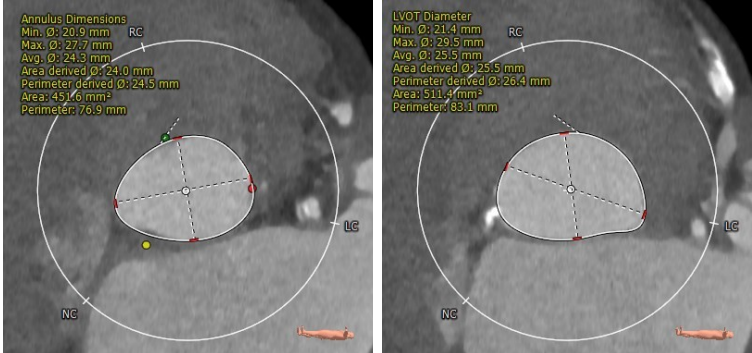

CTA主动脉根部解剖:

患者为三叶瓣,轻度钙化,右冠开口高度较高,升主动脉最宽处约33.2mm,横位心,心脏角度约62°,左室偏小。

Annulus Dimensions ——24.5mm

LVOT——25.5mm

Sinus——32.6*34*28.9mm

Stj——30.5mm

升主最宽处:33.2mm

心脏角度:62°

该病例为三叶瓣,瓣环直径24.5mm,左冠开口高度12.2mm,右冠开口高度17.4mm,升主最宽处达33.2mm,经核心实验室评估后 术中冠脉无堵塞风险,入路内径尚可,计划使用右侧股动脉为主入路,左侧股动脉为副入路。23mm球囊预扩张,使用Venus-A 29瓣膜。